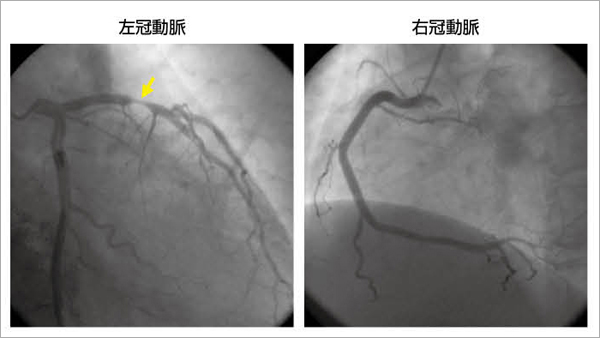

ファッション姫 通販 心エコーの最新動向 - 新。超音波診断 Vol.02 - 東芝メディカル その他

静脈エコー動画プラス (ハンズオンブック)

静脈エコー動画プラス (ハンズオンブック)